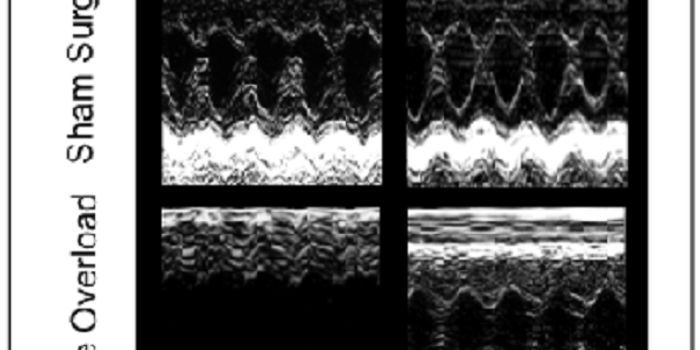

OCT 05, 2016CardiologyScientists reach roadblocks when they try to study diseases of the human heart merely because of its necessity for human ...

MAY 05, 2016CardiologyDilated cardiomyopathy (DCM) and hypertrophic cardiomyopathy (DCM) share some qualities in their tissue makeup and in th ...